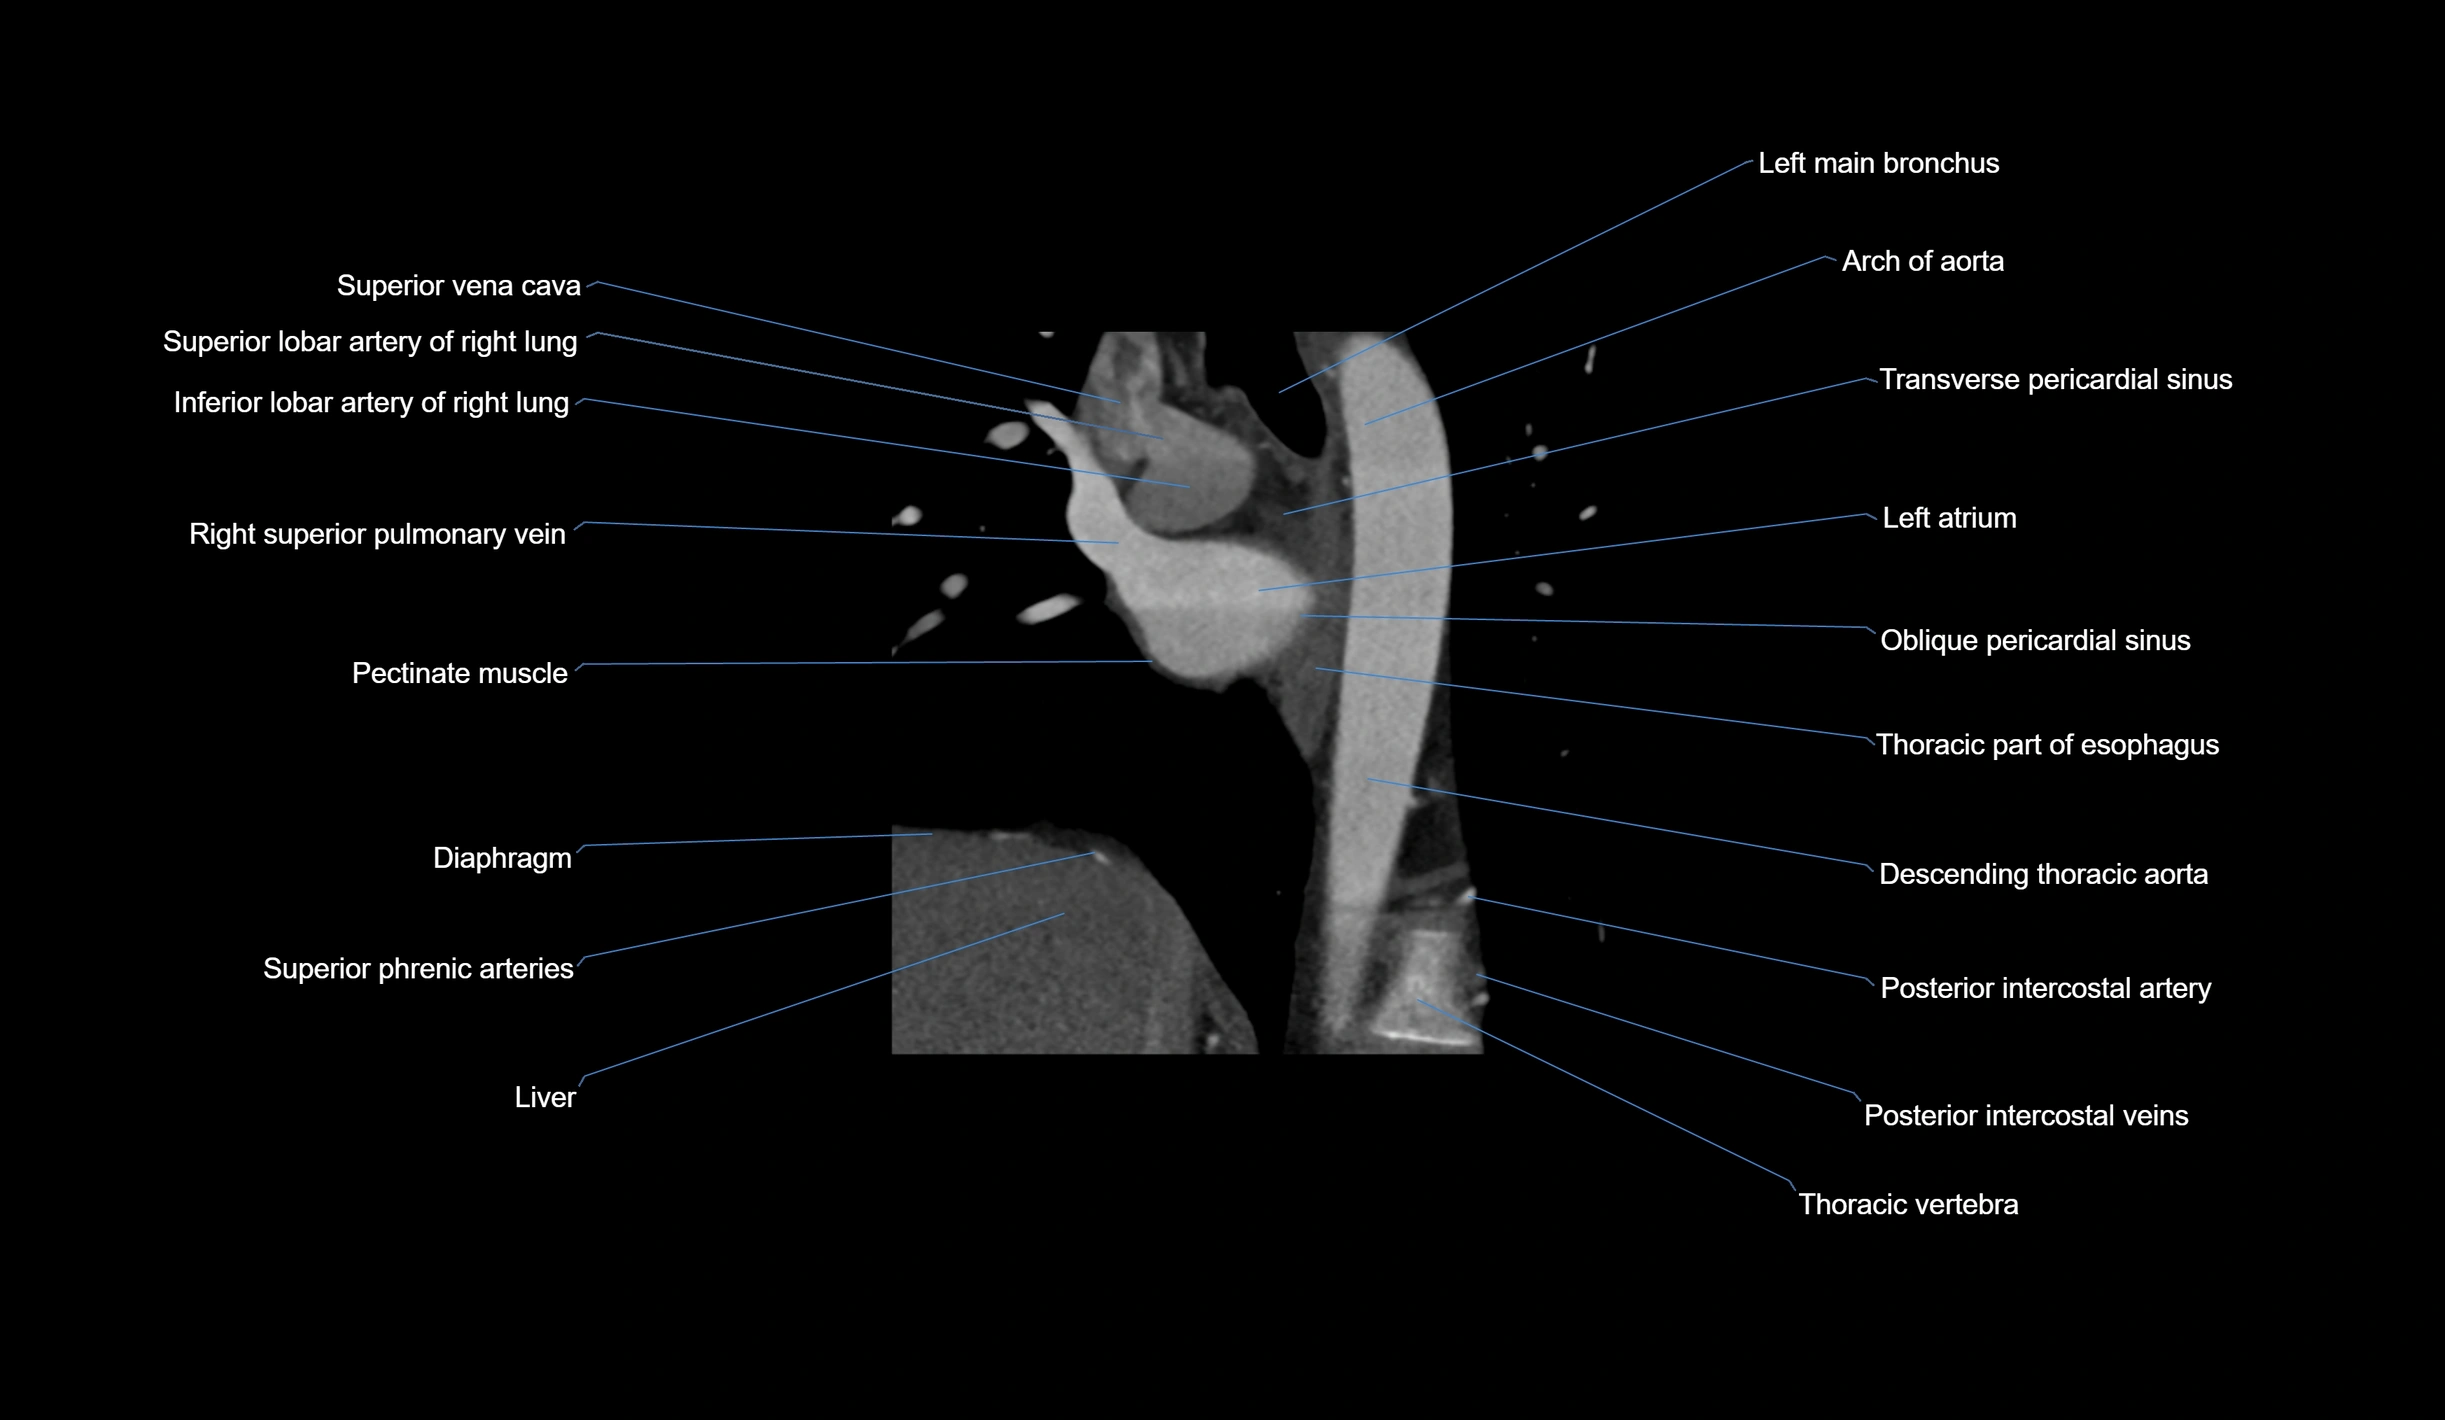

- Arch of aorta

- Descending thoracic aorta

- Left atrium

- Left main bronchus

- Oblique pericardial sinus

- Pectinate muscles

- Posterior intercostal arteries

- Posterior intercostal veins

- Right superior pulmonary vein

- Superior vena cava

- Transverse pericardial sinus